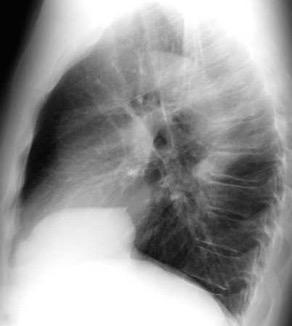

Parálisis frénica transitoria tras cirugía de válvula aórtica

Parálisis frénica transitoria post cirugía cardiaca (10%).

Puede acompañarse de atelectasia del LII.

Benjamin JJ et al. . Left lower lobe atelectasis and consolidation following cardiac surgery: the effect of topical cooling on the phrenic nerve. Radiology 1982

Atelectasia crónica de LLI en paciente con enfermedad neuromuscular.